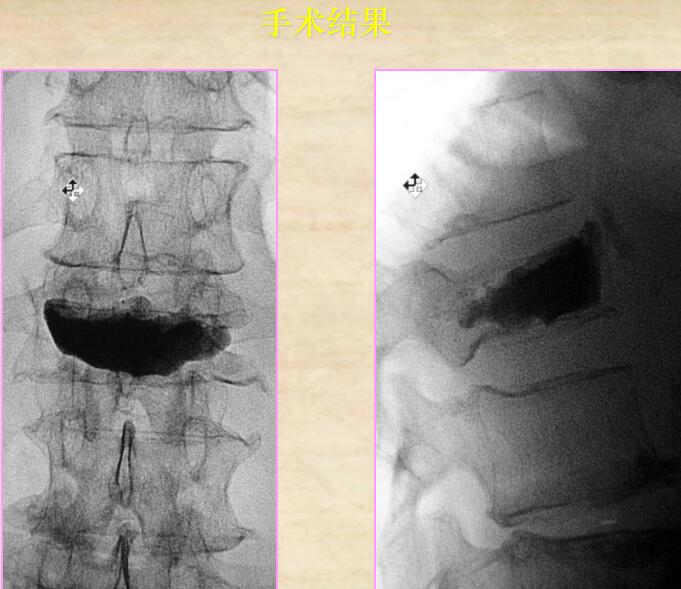

5、手術(shù)結(jié)果